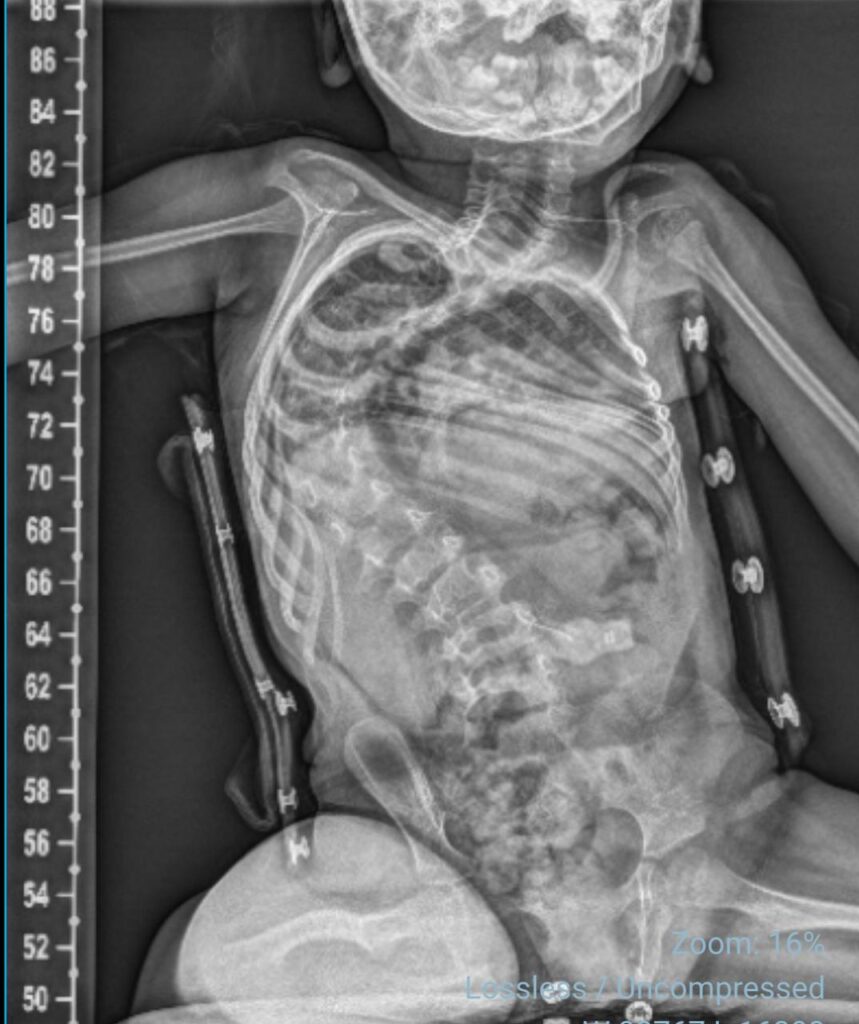

La familia de Sofía, una niña de cuatro años diagnosticada con Atrofia Muscular Espinal (AME), ha puesto en marcha una campaña solidaria con el objetivo de reunir los fondos necesarios para una cirugía de columna de carácter urgente. La menor presenta una escoliosis severa, condición asociada a su diagnóstico base, que requiere intervención quirúrgica para evitar un mayor deterioro en su salud y calidad de vida.

De acuerdo con la información entregada, la progresión de la escoliosis hace necesaria una intervención temprana para evitar complicaciones respiratorias y funcionales. Por ello, la familia solicita apoyo tanto económico como en la difusión de la campaña.